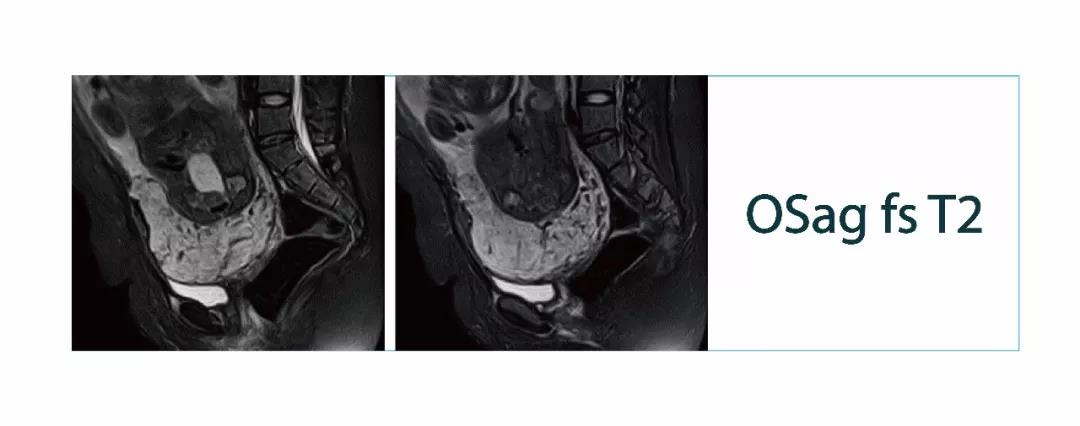

【朗润影像档案】磁共振影像病例分享(编号20180316)

【朗润影像档案】20180316磁共振影像病例结果讨论